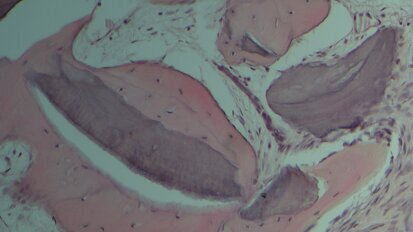

Caso di agenesia dentale trattato con impianti innovativi di diametro ridotto

Questo articolo descrive un caso di agenesia degli incisivi laterali superiori trattato mediante il posizionamento di impianti a diametro ridotto e con ...